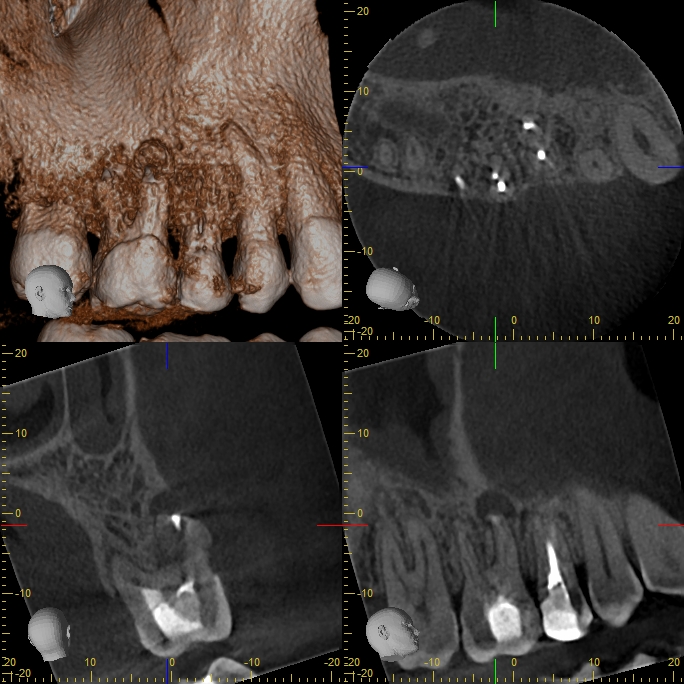

xyzview_20160929_185725

Revision nach Resektion